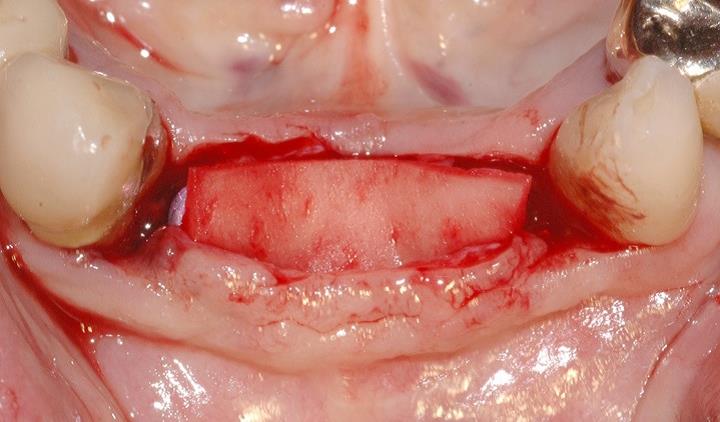

3/15 - Defect dimensions visible after full thickness flap preparationSoft tissue augmentation and GBR with mucoderm® and maxresorb® - Dr. S. Scherg